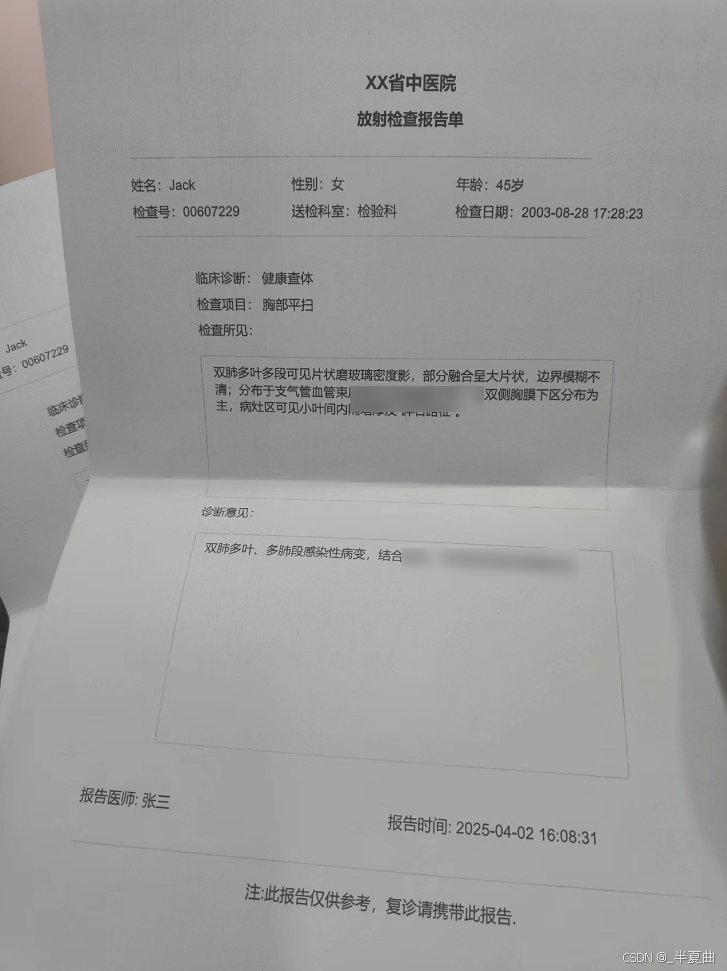

报告打印: